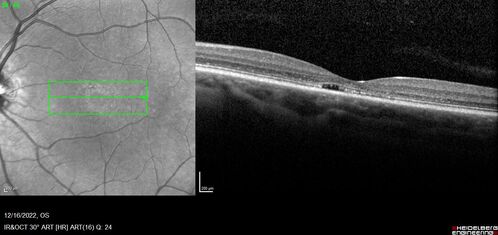

Stargardt Disease - Very Mild - 24 year old

This patient has 3 different ABCA4 mutations. His mother and sister have stargardts and his father has RP. His sisters images are also on Retinagallery.com